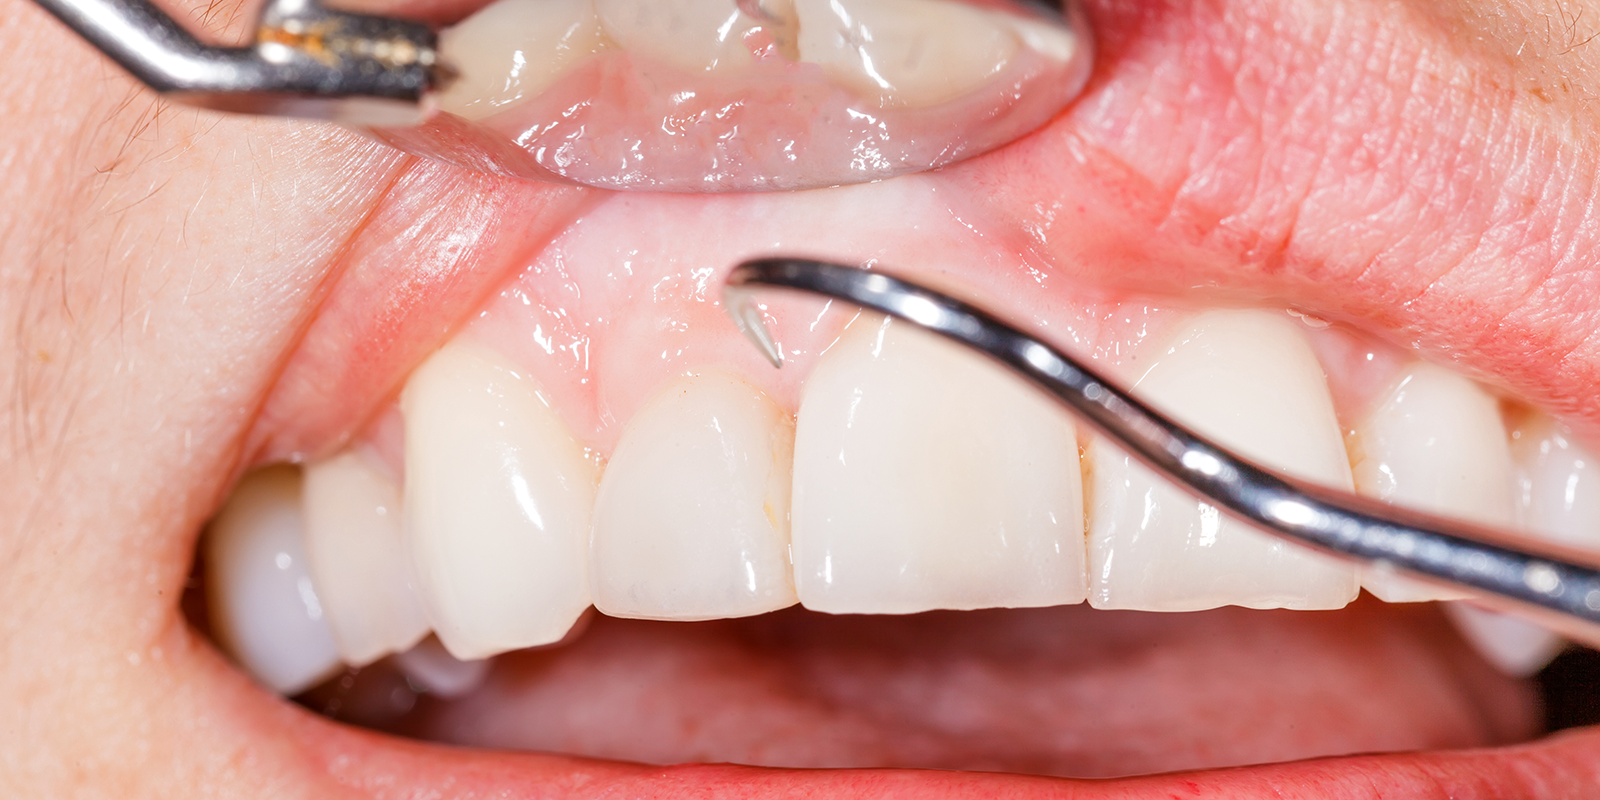

毎日のセルフケアに加えて、歯科医院での定期的なプロフェッショナルケアが歯周病予防には欠かせません。歯ブラシやフロスでは除去できない歯石を取り除くことができるからです。

歯石とは、プラークが唾液中のカルシウムやリンと結合して石のように硬くなったものです。歯石の表面はざらざらしているため、さらにプラークが付着しやすくなり、歯周病を悪化させる要因となります。特に歯茎の下に形成される「歯肉縁下歯石」は、病原性の高い歯周病菌の温床となります。

専門的クリーニングでは、「スケーリング」という処置で歯石を除去し、「ルートプレーニング」という処置で歯根の表面を滑らかにします。また、「PMTC(Professional Mechanical Tooth Cleaning)」という方法では、専用の器具とペーストを使用して、歯の表面に付着したバイオフィルムを徹底的に除去します。